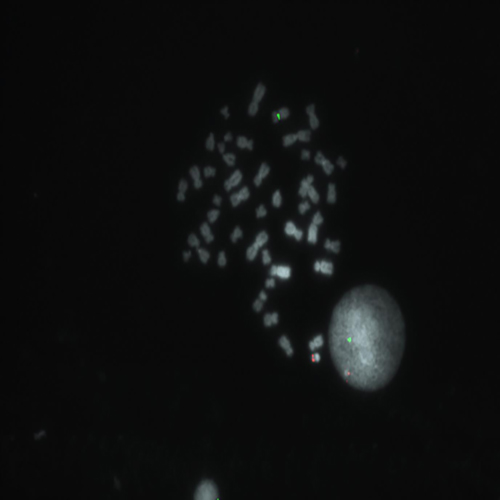

Hybridization of SE X / SE Y probe to a male metaphase spread showing normal pattern (1R1G).